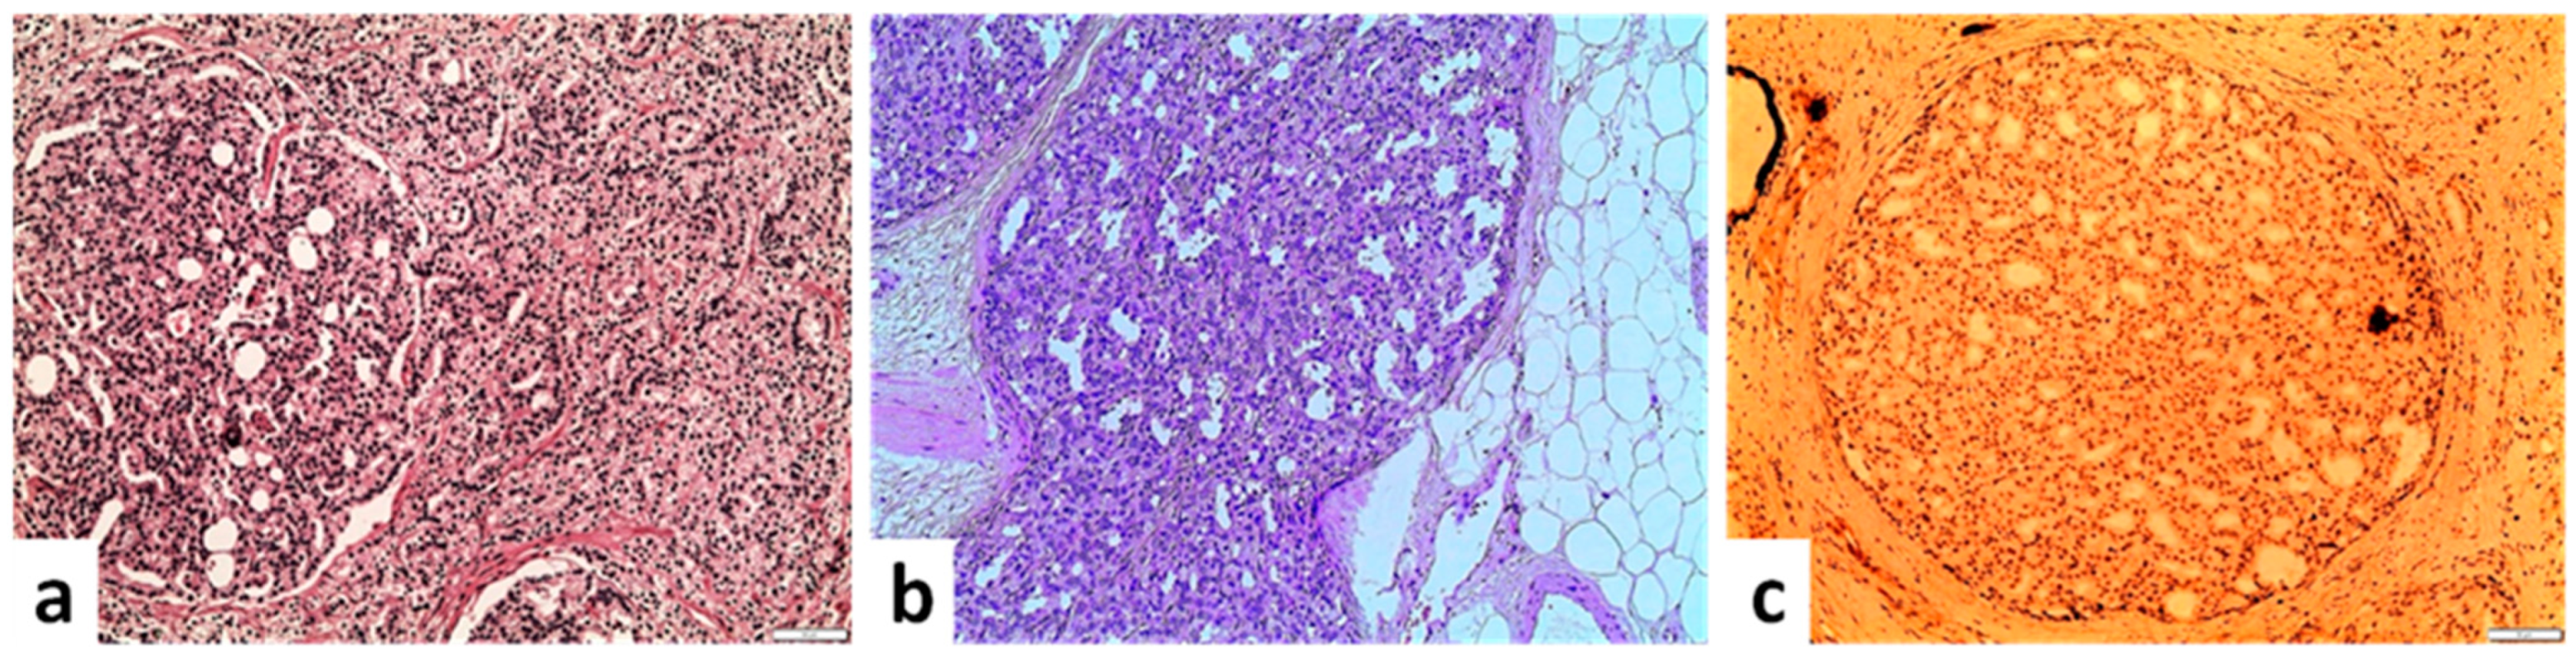

5. Malignant Cribriform Formations

5.1. Intraductal Carcinoma (IDC)

5.2. Invasive Acinar Carcinoma with Cribriform Pattern

5.3. Ductal Carcinoma

5.4. Basal Cell Carcinoma